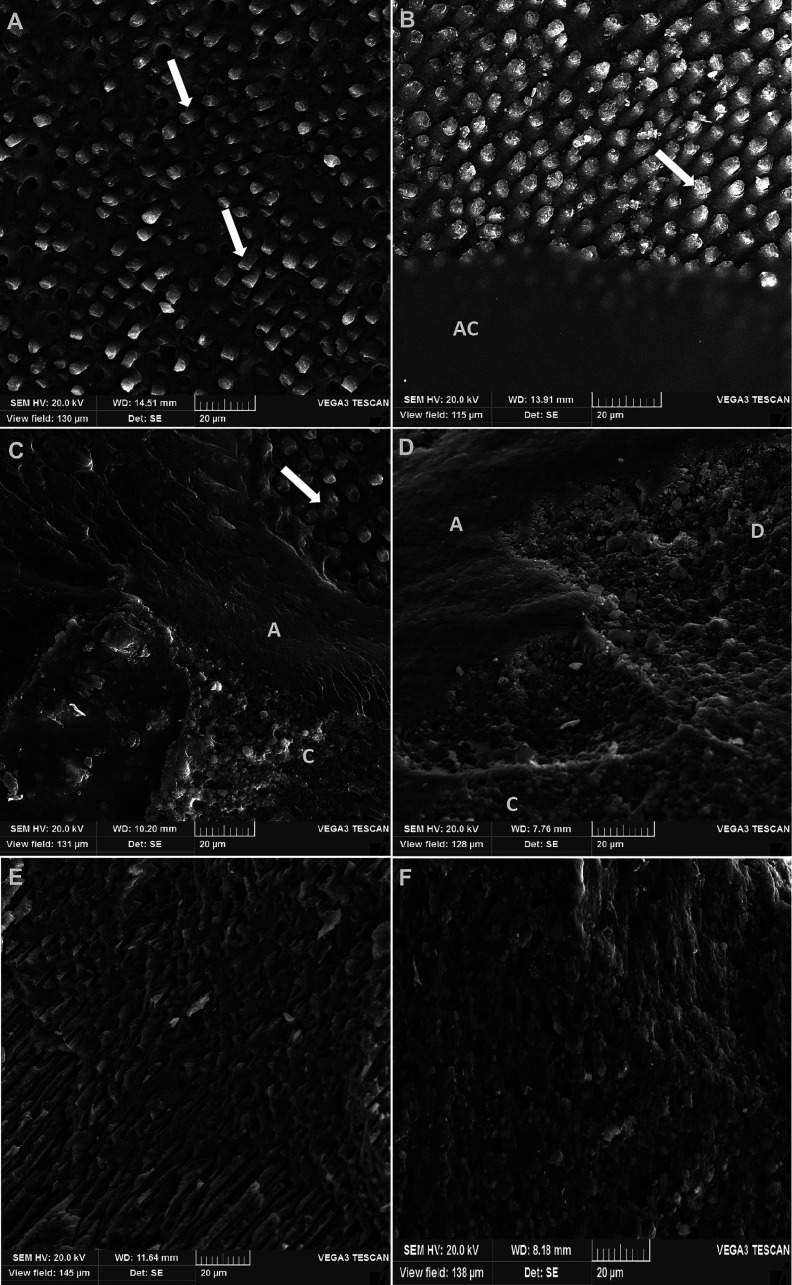

Material and methods: Red propolis extract was added to an experimental methacrylate-based adhesive (EA) at following concentrations: 100 (EA PV100), 250 (EA PV250) e 500 μg/mL (EA PV500). Single Bond Universal adhesive (SB) and EA without propolis were used as controls. The effectiveness of the dentin sealing was evaluated at nanoscale (silver uptake) and microscale (dye microleakage). Microtensile bond strength (µTBS) was measured 24 hours after the bonding process. Data were analyzed by one-way ANOVA and Tukey's test (α=0.05).

Results: EA PV500 showed the best coronal sealing, with better performance than the control and the commercial adhesive. Immediate µTBS values ranged from 28.94 + 9.25 MPa (EA PV100) to 39.09 + 9.60 MPa (SB). Comparing SB and EA with propolis, a significant decrease in µTBS was noted (p<0.05). The EA without propolis had similar performance to SB (p=1.000).

Conclusions: Nanoleakage and microleakage were not eliminated in any of the groups, but EA PV500 µg/mL exhibited the best sealing ability, with superior performance compared to the control and commercial adhesive. A decrease in μTBS of AE with propolis was observed. Key words:Dentin-bonding agents, Propolis, Dental materials, Dental marginal adaptation.